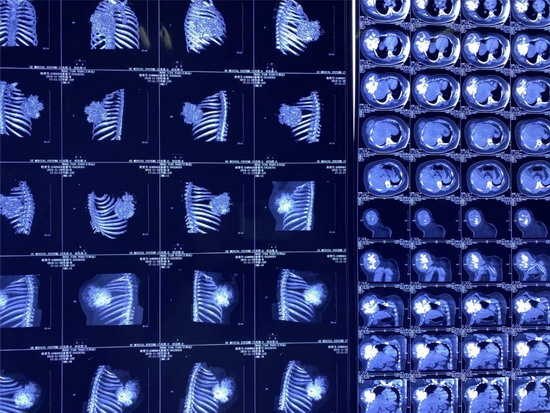

经专家的推荐,家人带着王某来到唐都医院胸腔外科就诊,CT检查显示右前胸壁肿瘤45×35厘米,穿刺活检结果为肋软骨源性恶性肿瘤。由于患者的软骨肉瘤恶性程度高,对放、化疗都不敏感,且易复发,手术切除是首选方案。此外,考虑到患者要切除五根肋骨,术后右前胸壁缺损大,医生决定采用3D打印技术,为王某进行胸廓重建。

2019年10月,王某来到了江苏省东台市某医院做了胸部CT检查。检查结果显示:王某右侧胸壁长了一个外径约45cmX36cm的巨型肿瘤,其右前肋骨骨质已经遭到破坏,医生考虑是软骨肉瘤。

2019年10月,王某来到了江苏省东台市人民医院,做了胸部CT检查。检查结果显示:王某右侧胸壁长了一个外径约45cmX36cm的巨型肿瘤,其右前肋骨骨质已经遭到破坏,医生考虑是软骨肉瘤。

2019年12月9日,小田来到唐都医院就诊,主管医生杨三虎为小田做了CT检查,显示右前胸壁巨大肿瘤,大小是45cm×35cm,鸡蛋大小的包块已经长成篮球大小的肿瘤,穿刺活检诊断为肋软骨源性恶性肿瘤。

黄立军副主任认为,要把肿瘤切干净,必须进行肿瘤的扩大切除(距离肿瘤3公分以上称为扩大切除),以避免肿瘤复发。其次,肿瘤切除也必须切掉5根肋骨(4-8前肋),小田胸部就留下了一个“大坑”—胸壁巨大缺损,小田本身块头大、体重大(130公斤)、肿瘤大,这三“大”特征加上胸壁巨大缺损使胸腔脏器得不到保护,会出现反常呼吸,甚至呼吸衰竭威胁生命。因此,肿瘤切除后,约1200平方厘米的巨大胸壁缺损重建是治疗的重中之重。